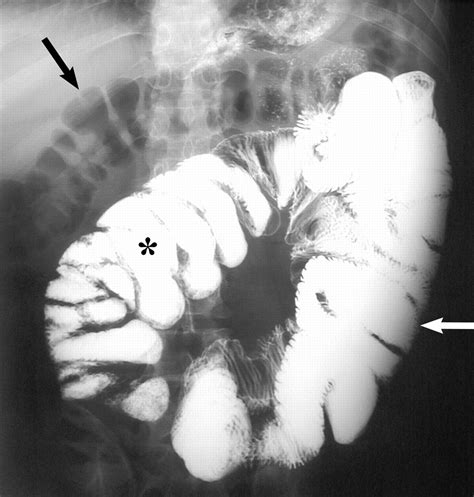

• Barium Ingestion: The patient ingests a barium solution, which coats the lining of the small intestine. Barium is a contrast agent that makes the small intestine visible on X-ray images.

• X-Ray Imaging: A series of X-ray images are taken at regular intervals as the barium moves through the small intestine. This allows radiologists to observe the movement and structure of the small intestine.

• Mucosal Pattern: The appearance of the lining of the small intestine, which can indicate inflammation or other abnormalities.

• Structural Abnormalities: Any visible abnormalities such as strictures, fistulas, or masses that may indicate disease.